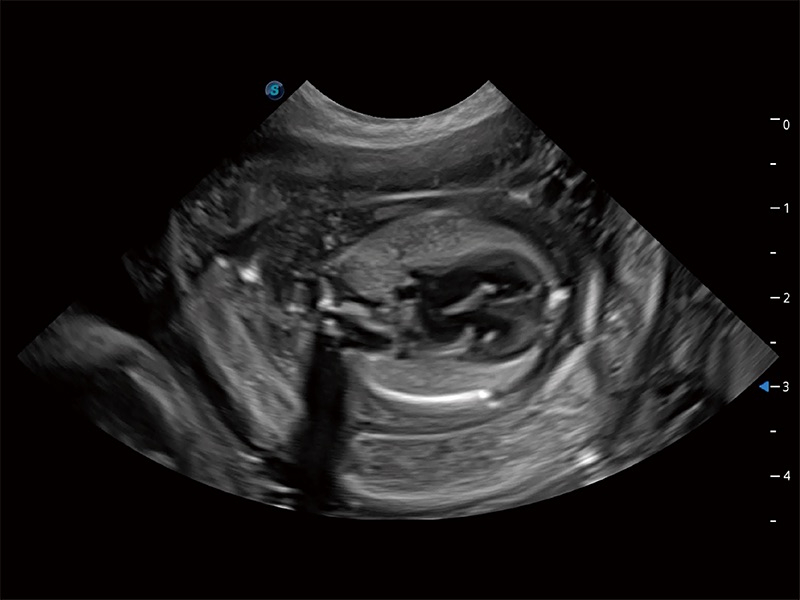

动物是人类最亲密的朋友和最值得信赖的伙伴。新葡的京集团8814检测站也一直致力于探索动物专用的超声影像解决方案。全新推出的ProPet系列,是新葡的京集团8814检测站在动物超声影像智能化、专业化、精准化的一次跨越式革新。动物不能用言语来表述自己的不适,通过超声影像,ProPet系列搭建了动物医生与不同物种沟通的“桥梁”,为动物医生注入了“治愈之力”。 ProPet 80 是新葡的京集团8814检测站匠心打造的一款高端动物专用彩超,采用性能卓越的全新硬件架构,极大提升超声系统的运行效率和数据处理能力,帮助动物医生从容应对日益增多的挑战性病例和日益多样化的临床需求。

高性能和先进的临床应用工具可以为动物医生提供临床信心。ProPet 80 搭载了先进的腹部和浅表应用工具,帮助医生在日常临床实践中发挥前所未有的作用。